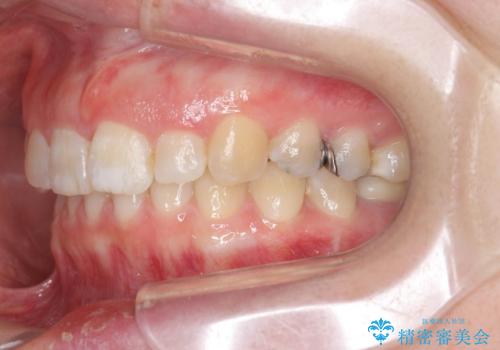

- 大きくねじれた前歯をまっすぐに並べたい。と矯正治療を希望され来院されました。

前歯をきっちり並べるには奥歯の噛み合わせの調整を行い上下の前後的関係を治し、ねじれを取るスペースを確保していきます。

当初前歯だけ治れば良い、という心算で来院されましたが奥歯の噛み合わせも負担が大きく問題の起きやすいことをお伝えし上顎の奥歯をきっちりと後方移動行い噛み合わせの調整を行いました。・